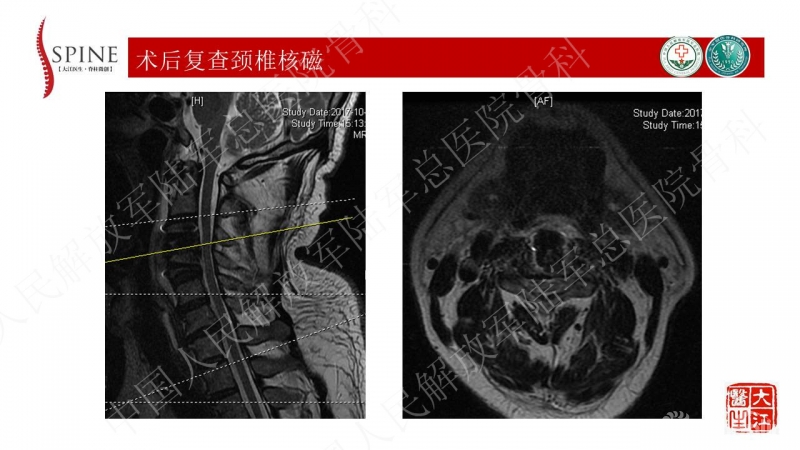

3月前骑车被汽车撞倒,额面部着地,伤后出现双上肢剧烈疼痛,双上肢肌力减弱,以手内肌为主,活动受限,诊为“急性中央型颈脊髓损伤”,后全麻下行“颈前路颈3/4椎间盘切除椎间植骨融合术” 术后患者双上肢症状恢复良好,出院后离床活动即感腰痛剧烈,行走约100米感双下肢疼痛,疼痛主要位于双侧小腿后方,右侧为著,休息后可缓解,但体位改变疼痛加重

患者缺乏X光片颈椎管椎管比值的测量,但基本可见患者有明确的发育性颈椎管狭窄,又有颈椎退变增生的病理基础,核磁见多节段的颈脊髓压迫,近期出现右上肢疼痛麻木症状,体格检查脊髓和单一神经根损害表现,为混合型颈椎病(脊髓型/神经根型)。可考虑行颈椎管扩大成形术,包括单开门/双开门等方式,结合单一神经管切开减压,可达到全面的治疗效果。